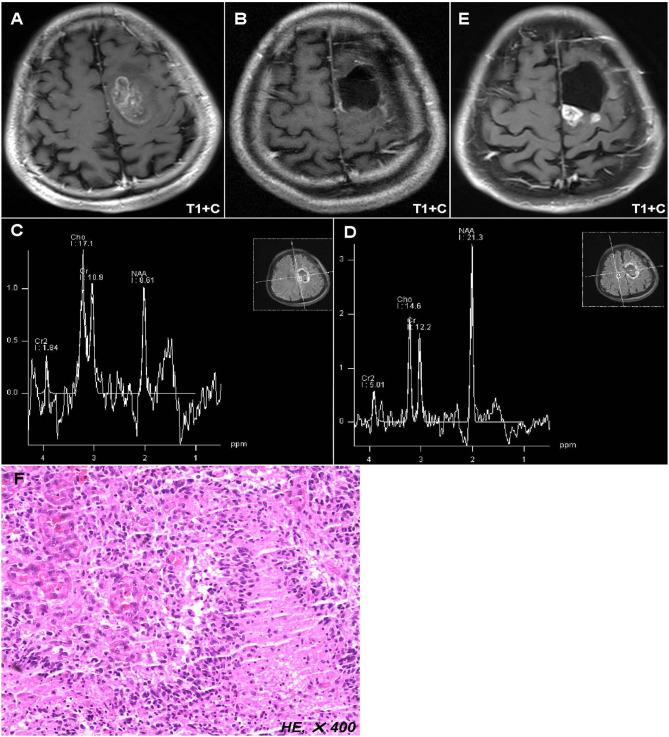

To explore the prognostic significance of metabolic parameters in postoperative peritumoral edema zone (PEZ) of patients with glioblastoma (GBM) based on proton magnetic resonance spectroscopy (MRS). The postoperative MRS data of 67 patients with GBM from Beijing Tiantan Hospital were retrospectively reviewed. Metabolite ratios including Cho/NAA, Cho/Cr, and NAA/Cr in both postoperative PEZ and contralateral normal brain region were recorded. Log-rank analysis and Cox regression model were used to identify parameters correlated with progression-free survival (PFS) and overall survival (OS). Compared with the contralateral normal brain region, postoperative PEZ showed a lower ratio of NAA/Cr (1.20 ± 0.42 vs. 1.81 ± 0.48, < 0.001), and higher ratios of Cho/Cr and Cho/NAA (1.36 ± 0.44 vs. 1.02 ± 0.27, < 0.001 and 1.32 ± 0.59 vs. 0.57 ± 0.14, < 0.001). Both the ratios of Cho/NAA and NAA/Cr were identified as prognostic factors in univariate analysis ( < 0.05), while only Cho/NAA ≥ 1.31 was further confirmed as an independent risk factor for early recurrence in the Cox regression model ( < 0.01). According to the factors of MGMT promoter unmethylation, without radiotherapy and Cho/NAA ≥ 1.31, a prognostic scoring scale for GBM was established, which could divide patients into low-risk, moderate-risk, and high-risk groups. There was a significant difference of survival rate between the three groups ( < 0.001). Higher Cho/NAA ratio in the postoperative PEZ of GBM predicts earlier recurrence and is associated with poor prognosis. The prognostic scoring scale based on clinical, molecular and metabolic parameters of patients with GBM can help doctors to make more precise prediction of survival time and to adjust therapeutic regimens.

摘要